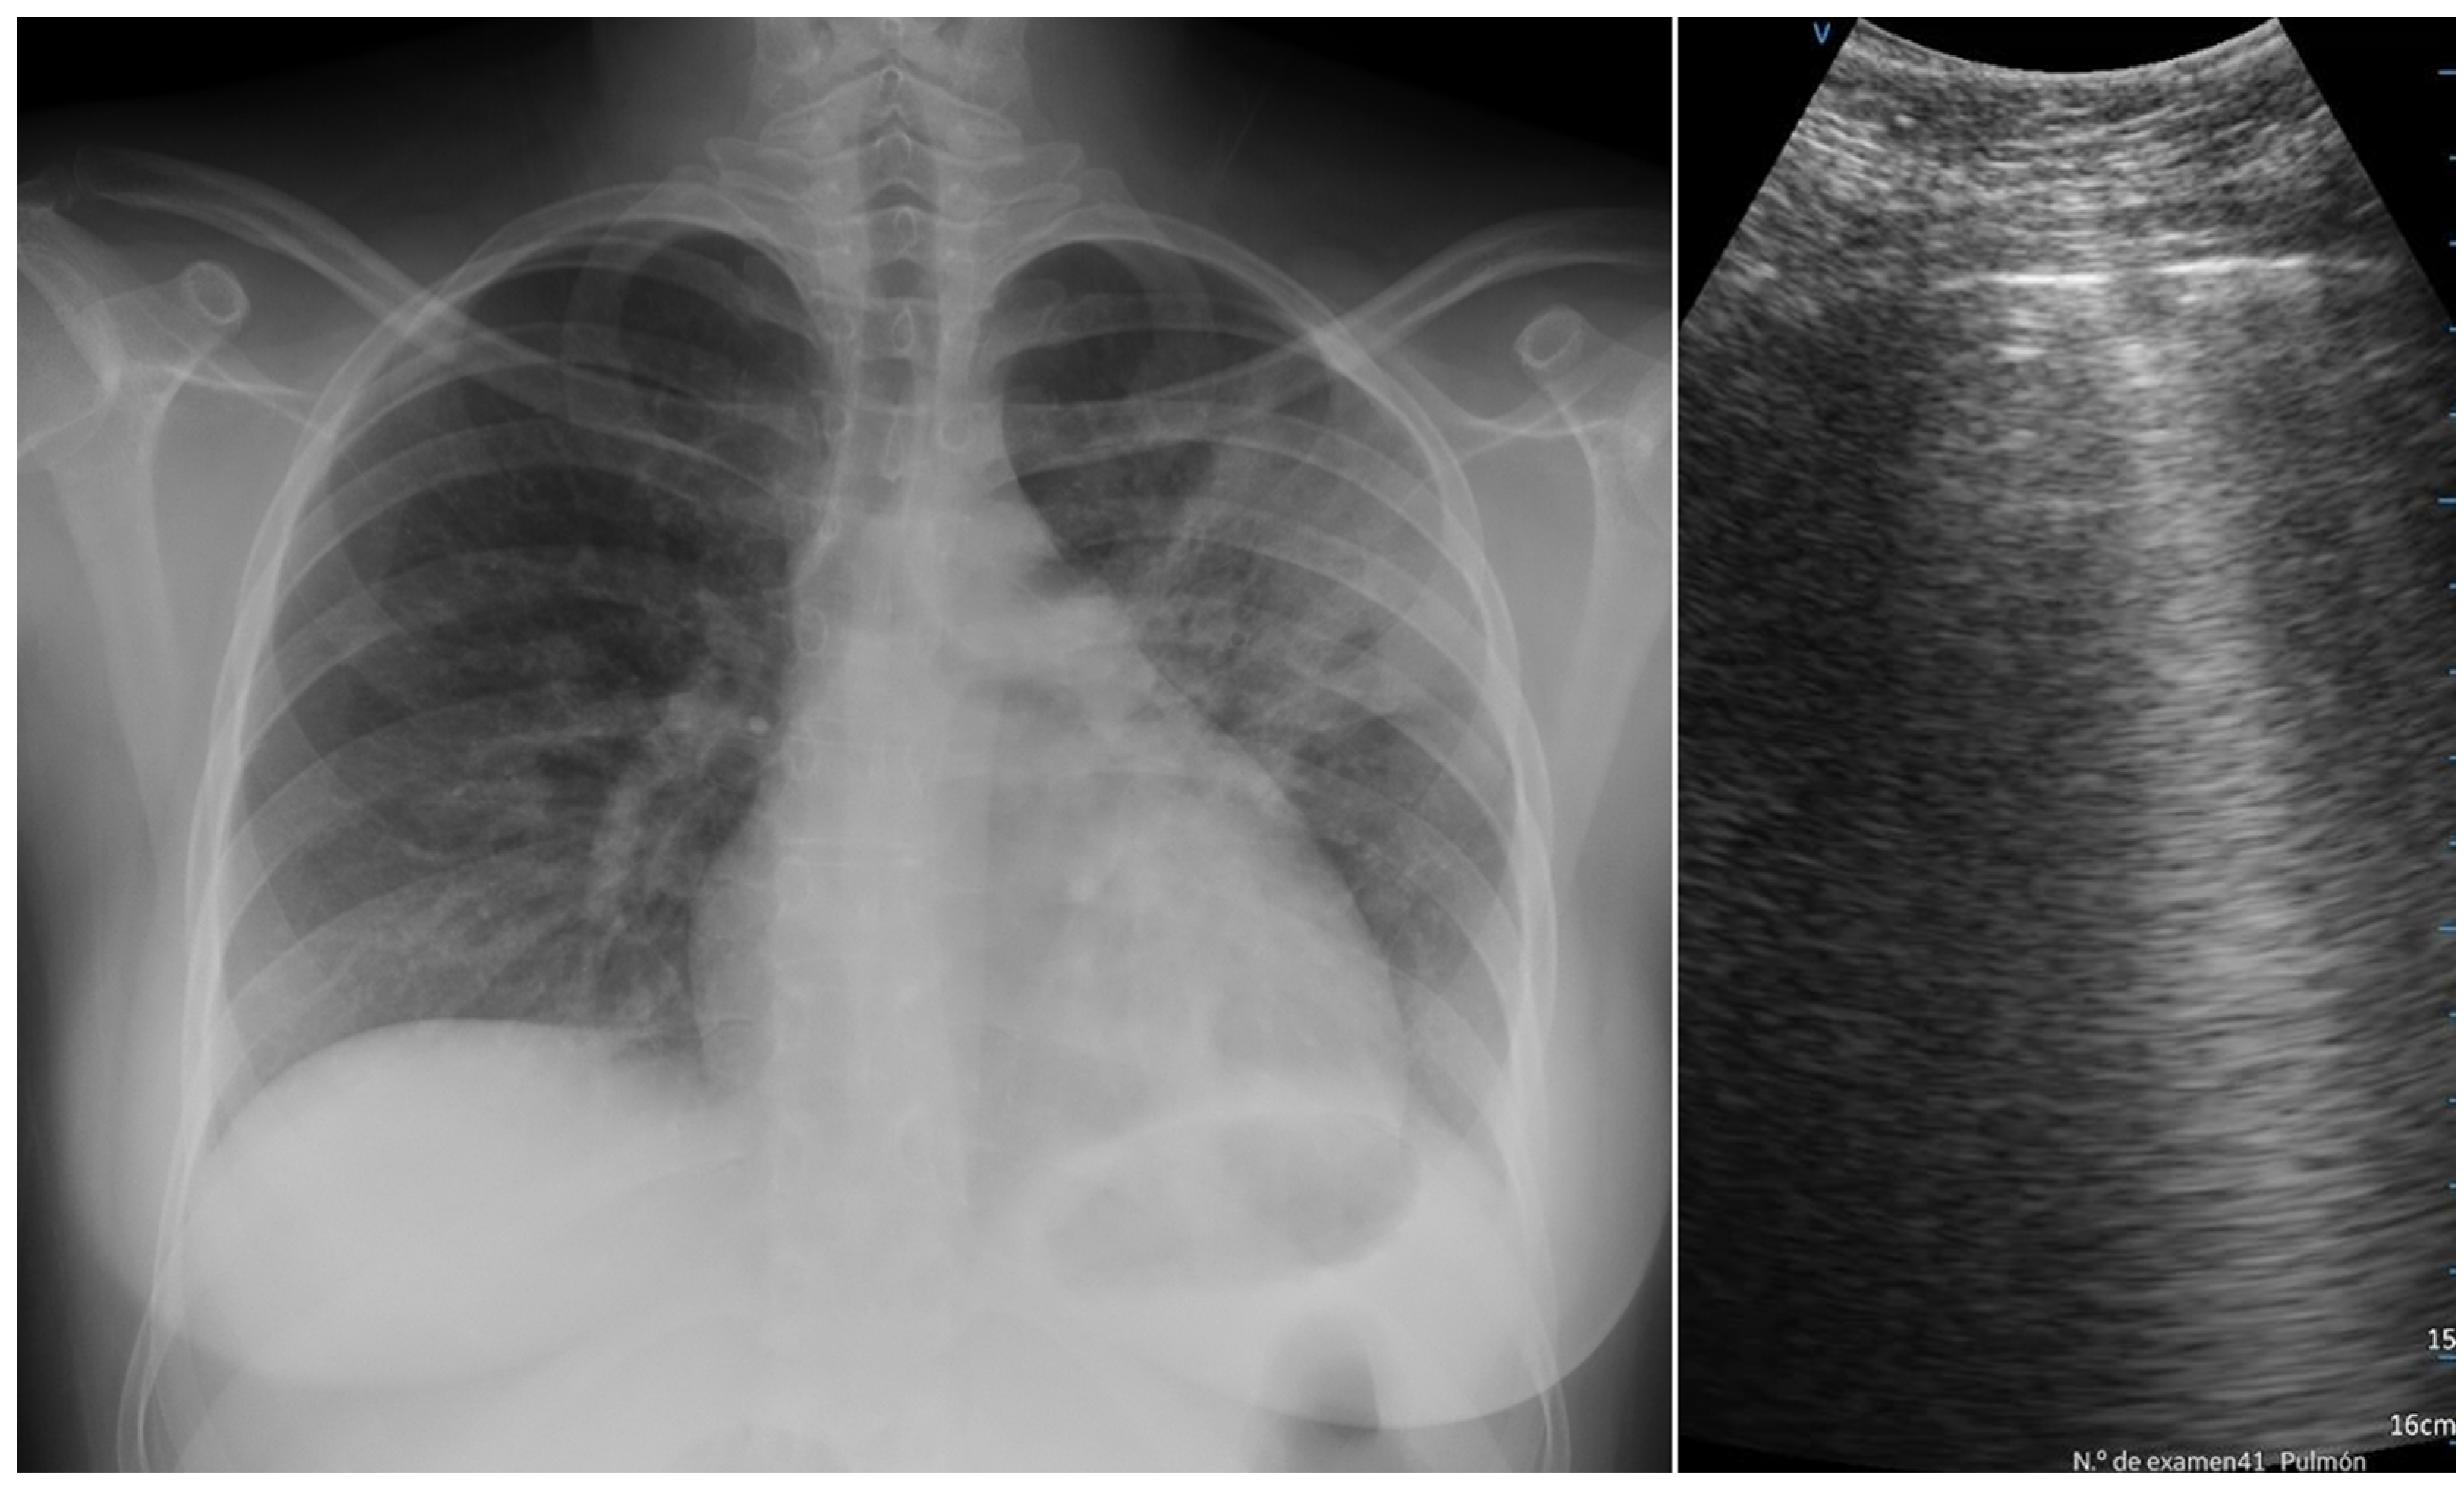

| X-ray normal findings | 17.0% | 26.5% | ns |

| X-ray ground glass | 35.6% | 35.5% | ns |

| X-ray interstitial pattern | 61.9% | 29.4% | <0.001 |

| X-ray no infiltrate | 27.2% | 32.3% | ns |

| X-ray unilateral infiltrate | 23.3% | 11.8% | ns |

| X-ray bilateral infiltrate | 49.5% | 55.9% | ns |